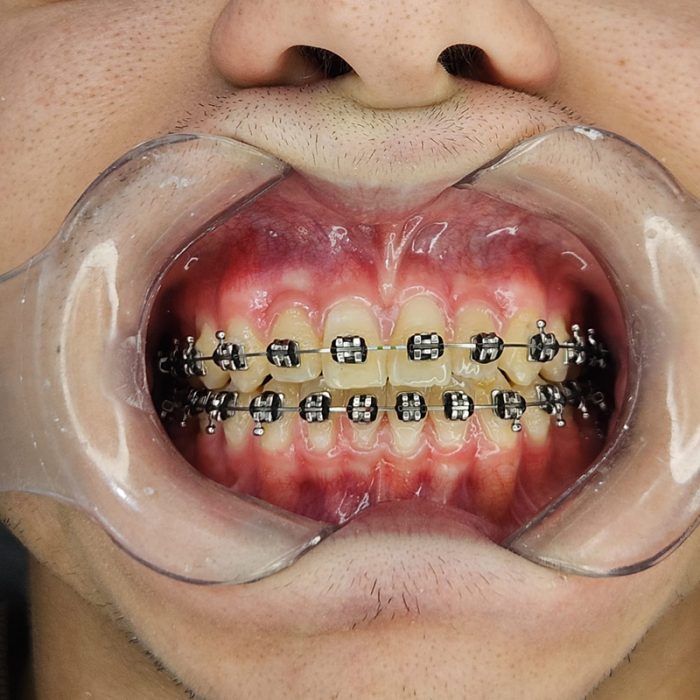

Ortopedia & Ortodontia

Alinhadores, aparelhos estéticos, aparelhos ortopédico e convencional.

Desconforto com aparelho mal ajustado